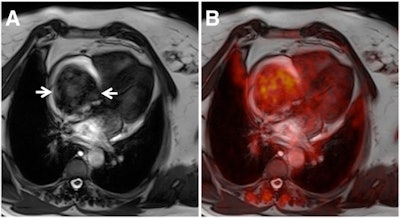

The ability of FDG-PET/MRI to detail morphology and assess malignancy makes it a "powerful tool" for the diagnostic workup of cardiac tumors, but it should be used judiciously because of its high cost and limited availability, according to a new study from Germany in the February Journal of Nuclear Medicine.

Led by Dr. Felix Nensa from the department of diagnostic and interventional radiology and neuroradiology at University Hospital Essen, the study found that FDG-PET and MRI separately achieved sensitivity of 100% and specificity of 92% in determining tumor malignancy. When the two modalities were combined, both sensitivity and specificity reached 100% for diagnosing malignancy (JNM, February 2015, Vol. 56:2, pp. 255-260).

Previous studies of pathology outside the heart have found that FDG-PET with MRI can provide "superior morphologic tumor characterization and visualization of tumor metabolism," Nensa and colleagues wrote. Thus, they chose to explore the hybrid modality for cardiac tumors, comparing it with the use of MRI and FDG-PET alone.

Two board-certified radiologists with more than 10 years of experience in cardiac MRI and oncologic PET interpreted the results and found that the maximum standardized uptake value (SUVmax) in malignant lesions (13.2 ± 6.2) was significantly higher than in nonmalignant cases (2.3 ± 1.2).

A threshold of 5.2 or greater SUVmax resulted in 100% sensitivity and 92% specificity for differentiating malignant from nonmalignant lesions.

The authors concluded that independently interpreted FDG-PET and MRI results produced sensitivity of 100% and specificity of 92% in determining tumor malignancy. A combination of FDG-PET and MRI achieved 100% sensitivity and 100% specificity, when both tests were required to be positive for diagnosing malignancy.

Based on the results, Nensa and colleagues concluded that FDG-PET/MRI is a "powerful tool" in the diagnostic workup of cardiac tumors -- with caveats.